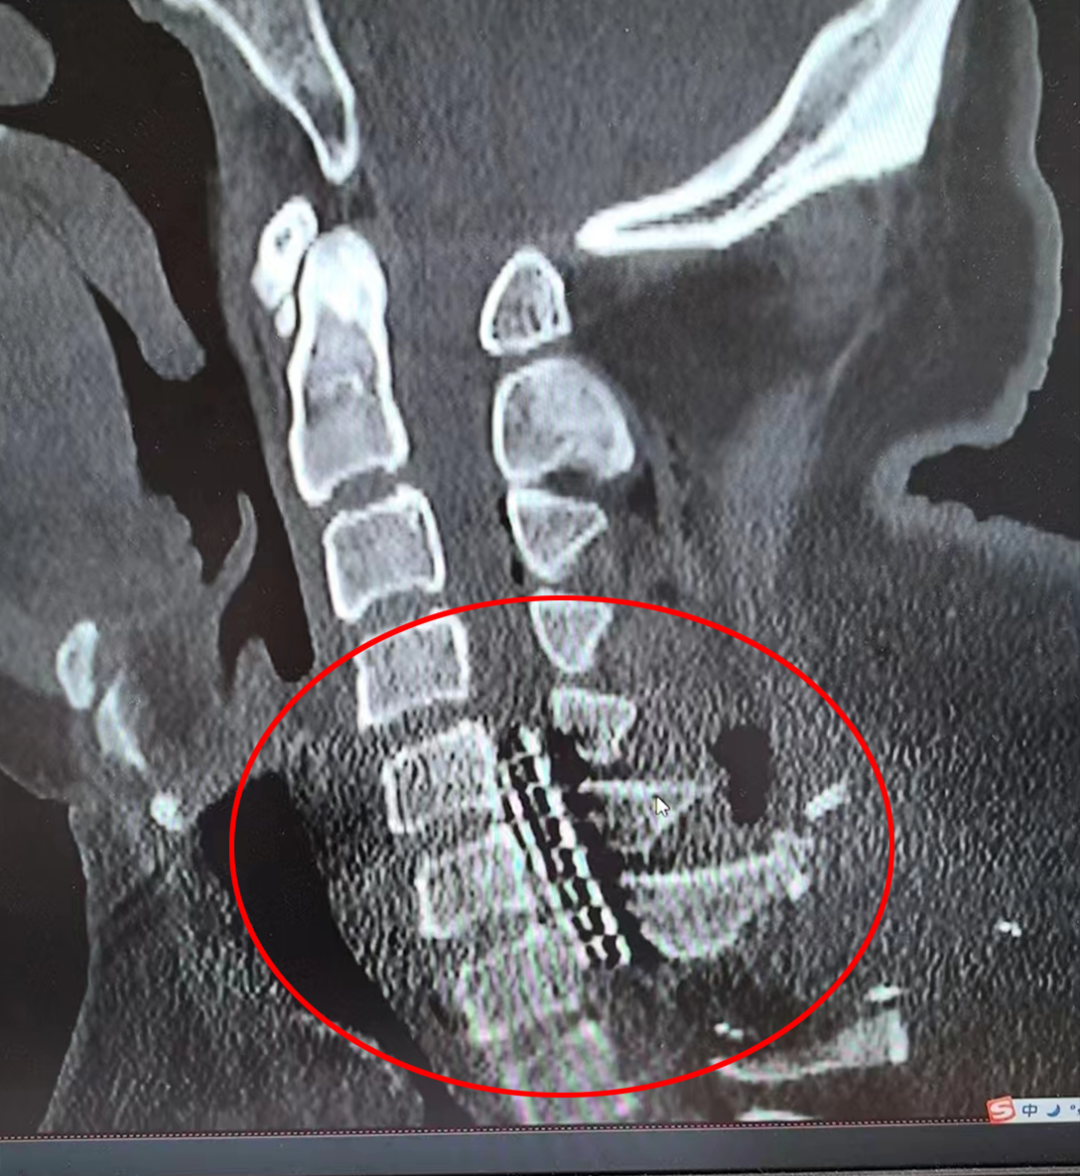

图片

▲术后复查电极植入位置精准